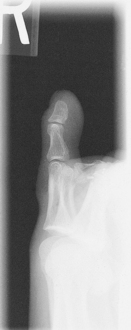

Alternative routine may include entire foot on AP toe projection for possible secondary trauma to other parts of foot (see AP foot).

• Patient prone with foot and great toe carefully dorsiflexed so the plantar surface forms a 15°–20° angle from vertical if possible (adjust CR angle as needed)

This may be a more tolerable position for patient to maintain if in great pain.